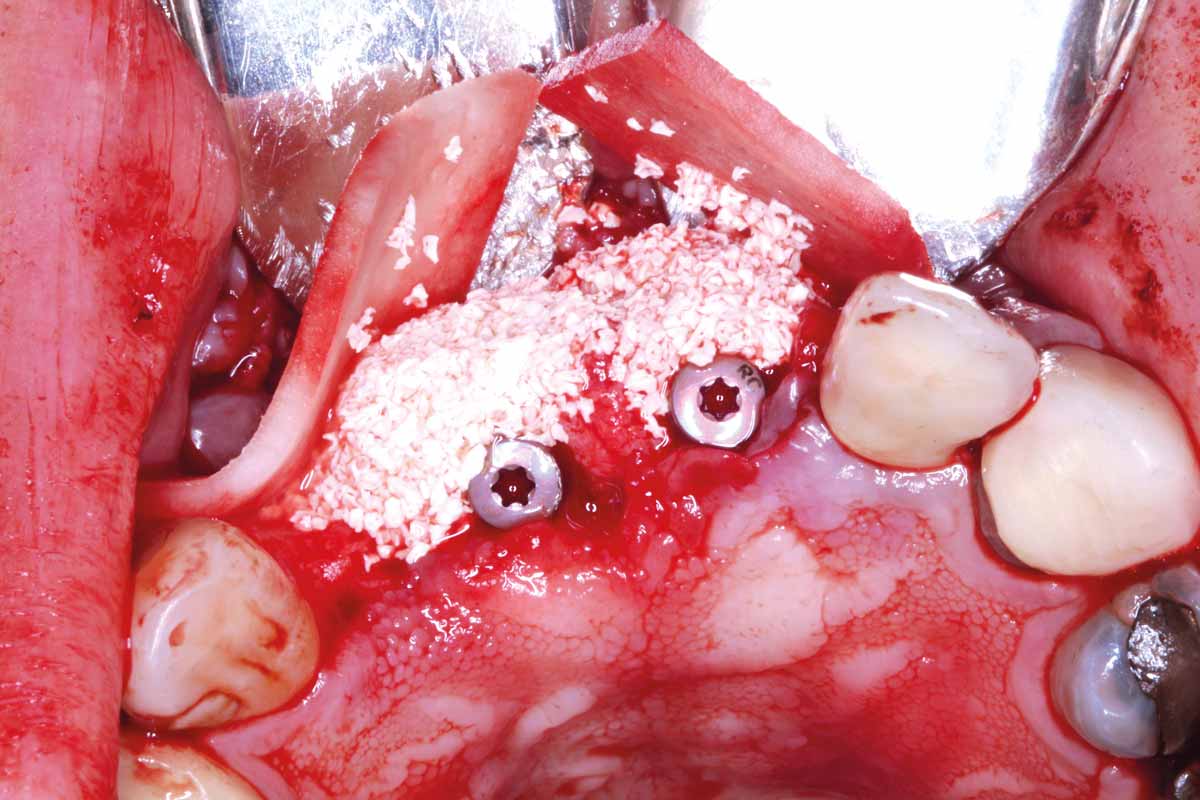

9/27 - GBR with autologous bone chips covered with small particles cerabone® and two mucoderm® used as a barrier membrane

GBR and soft tissue augmentation with cerabone® and mucoderm® - H. Maghaireh & V. Ivancheva